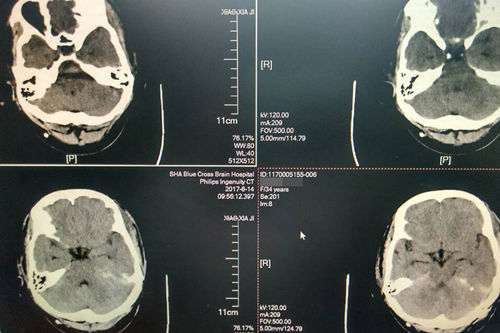

术后:CT显示肿瘤切除,小脑幕缘、右侧脑室渗出已吸收